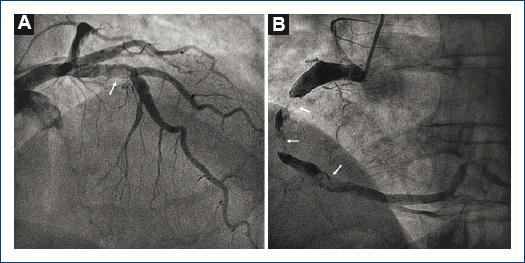

Se presenta el caso de un paciente de 62 años con antecedente de dislipemia bajo tratamiento con atorvastatina y aneurisma de la aorta abdominal, intervenido en fecha reciente con implante de endoprótesis aórtica (Endurant® 25 mm), que 10 días antes del alta hospitalaria solicitó atención médica domiciliaria por dolor torácico central opresivo intenso. En la primera valoración se obtuvo un electrocardiograma de 12 derivaciones que mostró elevación del segmento ST inferior, por lo que el paciente se trasladó al centro de los autores ante la sospecha de infarto agudo de miocardio (IAM). Se llevó a cabo una coronariografía urgente, que reveló ectasia coronaria difusa con un gran defecto de repleción en la arteria descendente anterior (ADA) a nivel proximal, consistente con trombosis no oclusiva, y una oclusión trombótica total (TIMI 0) en la arteria coronaria derecha (ACD) media, que era un vaso aneurísmico (Fig. 1A-B). El intervencionismo percutáneo en la ACD resultó ineficaz, a pesar de la tromboaspiración y múltiples insuflaciones del balón, y se concluyó el procedimiento con un flujo final TIMI II.

Figura 1 A: Hallazgos por angiografía en el árbol coronario izquierdo B: Coronaria derecha. Las flechas señalan amplios defectos de repleción indicativos de trombosis intracoronaria.